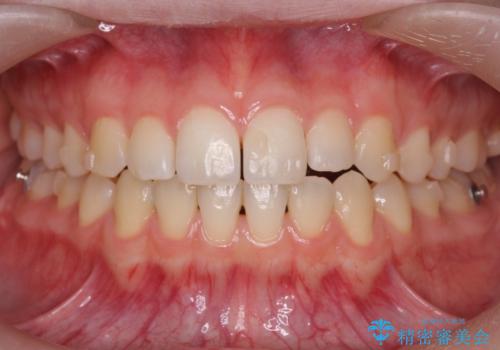

咬んでも前歯が閉じない 矯正治療で見た目を含めて改善

咬んでも向こう側が見える、前歯が閉じない症状でした。また、上の前歯が少し前に出ている状態でした。

上の前歯をわずかに削る処置を行い、後ろに下げながら下の歯となるべく咬むように矯正治療を行いました。